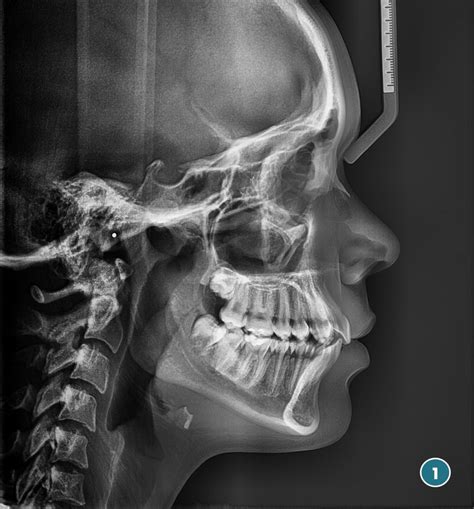

Figura 5 Telerradiografía lateral de cráneo pretratamiento.

La telerradiografía lateral de cráneo inicial (fig. 5) evidencia el resalte existente, con una mandíbula que presenta características típicas de tener un buen potencial de crecimiento.

Figura 6 Trazado cefalométrico pretratamiento.

Cefalométricamente, según Ricketts (fig. 6), encontramos un patrón mesofacial, con una maloclusión esquelética de Clase II de origen mandibular, con incisivos inferiores retroinclinados.